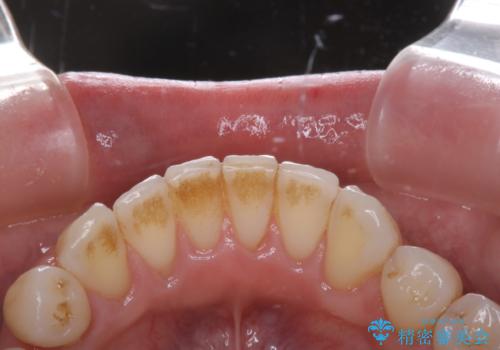

紅茶のステインをきれいにしたい

- 毎日紅茶を飲むため、歯のステインが気になるためキレイにしたいとのことでした。

PMTC60分コースを行いました。

PMTCは、歯に付着した汚れを除去していくため、着色が気になる場合にも行うことができます。ご自身でのセルフケアだけで着色を落とそうとすると、逆に歯を傷つけてしまったり、精密に汚れを除去できないこともあります。また、日常生活で着色しやすい飲食物を避けたりすることはストレスに感じてしまったり、あまり現実的ではありません。